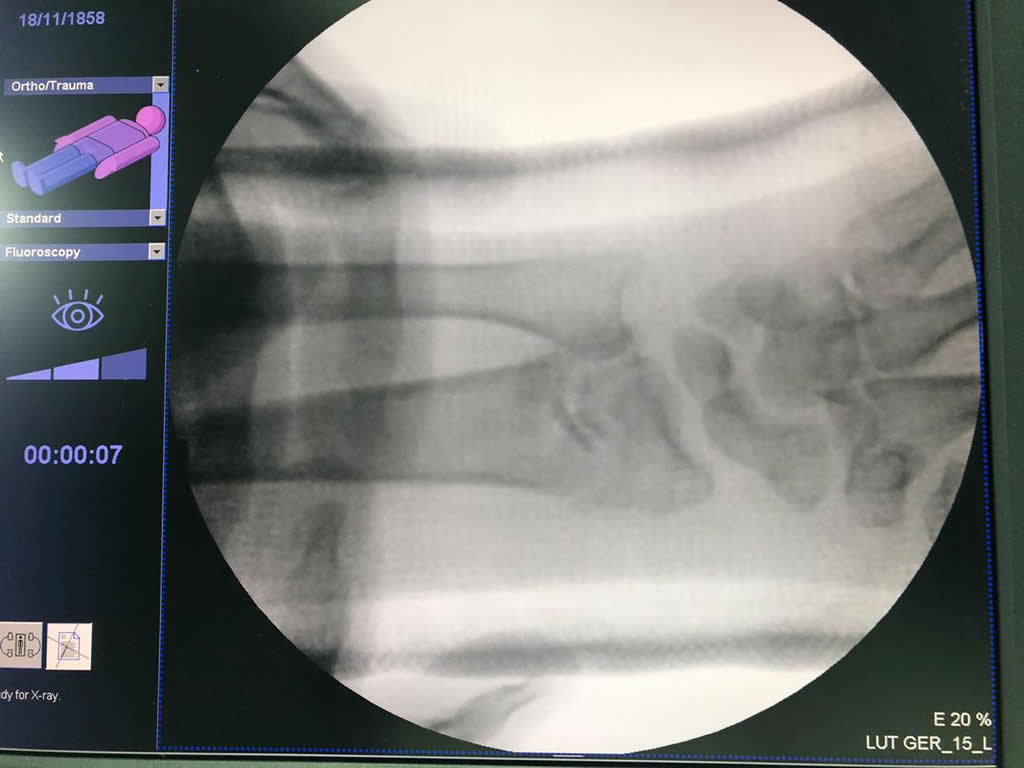

Húmero - Cirugías de Muñecas y Manos

Los procedimientos más comunes en cirugía de la mano son aquellos destinados a reparar traumatismos, incluyendo lesiones de tendones, nervios, vasos sanguíneos, y articulaciones; huesos fracturados; y quemaduras, cortes, y otros daños de la piel.